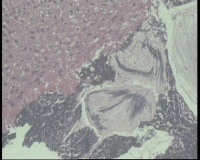

镜下见鳞状上皮大部分如(图1) ,仅局灶鳞状上皮异型(图2-4),细胞似牵拉变形,部分腺腔内见异型细胞团,这些细胞跟LEEP刀手术电凝有关系吗?这个怎么报?累腺明显,上皮图1怎么报?能报CINII—III累及腺体吗?还是宫颈高级别鳞状上皮内病变累及腺体

图4

CIN2-3累腺,有机械损伤,要按1-12点分别报告,要报告内外切缘情况。